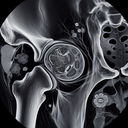

МРТ кульшових суглобів

МРТ кульшових суглобів — це неінвазивний метод дослідження, що забезпечує детальне зображення цієї ділянки. Він особливо корисний для оцінки стану м'яких тканин, таких як хрящі, зв'язки, сухожилля та м'язи, а також виявлення запалень, пухлин чи інших ушкоджень. **Переваги МРТ кульшових суглобів:** 1...